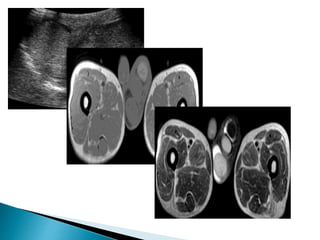

• #16 The testicle is typically low signal on T1 and high signal on T2. The normal testicle exhibits intense diffusion restriction, and these sequences can aid confident identification.

• #17 T1 and T2 weighted axial and coronal sequences, especially with a small field of view (FOV) are advisable as well as diffusion weighted imaging. The testicle is typically low signal on T1 and high signal on T2. The normal testicle exhibits intense diffusion restriction The hyperintensity is consistent with restricted diffusion The normal left testicle is identified lying within the left side of the scrotal sac.  The undescended smaller right testicle is intra-peritoneal in location, lying medial to the right external iliac vessels.

• #18  Transverse STiR images from MRI examinations of patients with undescended testicles (arrow) in the proximal end of the inguinal canal (A) suprapubic pouch (B) and pelvis (C).